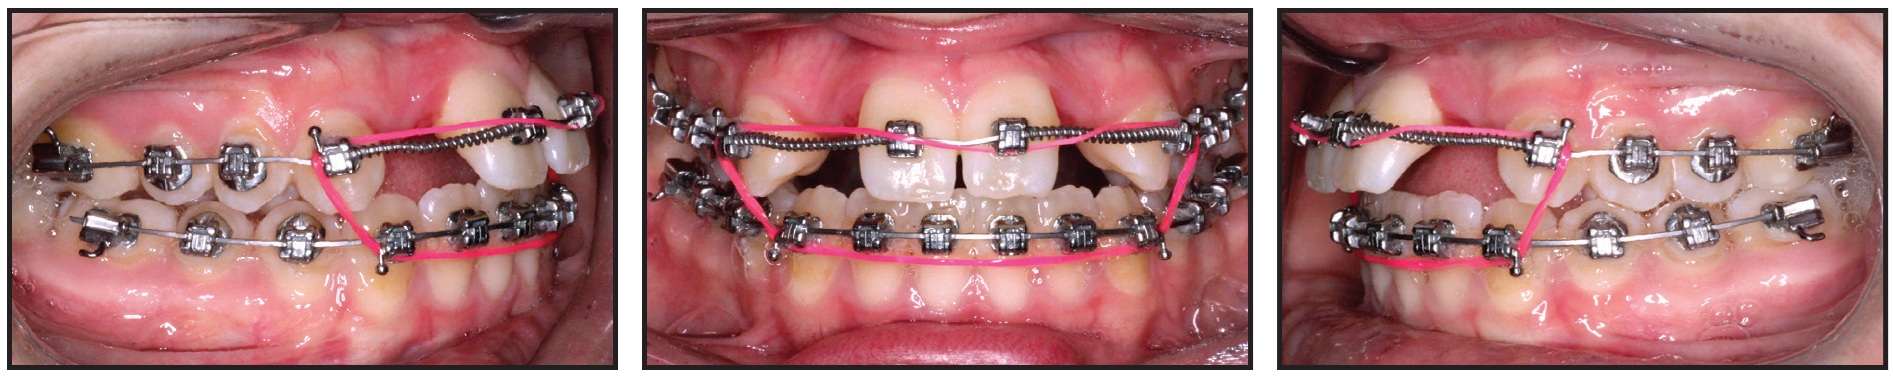

This 16-year-old female presented with a maxillary deficiency and missing upper lateral incisors (Fig. 16).

Fig. 16 16-year-old female patient with maxillary deficiency and missing upper lateral incisors before treatment.

After consultation with a maxillofacial surgeon and restorative dentist, she declined orthognathic surgery. The orthodontic treatment objectives were to align the teeth and open spaces for implant restoration of the lateral incisors without iatrogenic worsening of the open-bite tendency. A low-torque bracket prescription was selected, the second molars were not included in the archwire, and light vertical anterior elastics were worn at night. No restorative material was placed on the occlusal surfaces of the posterior teeth to disclude the bite. The 14-month progress records demonstrated an improvement in the occlusion and adequate space for implant placement, although further root parallelism was needed (Fig. 17).

Fig. 17 After 14 months of treatment, showing improved occlusion and adequate space for implant placement.